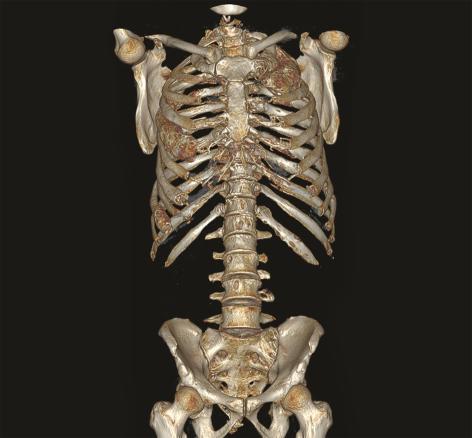

Les images de scanner (fig. 3-5) mettent en évidence de multiples lésions soufflantes avec un aspect en verre dépoli de l’os trabéculaire refoulant la corticale ainsi qu’une érosion marquée de la corticale, sans réaction périostée, confirmant une dysplasie fibreuse polyostotique prédominant au niveau des côtes et du rachis, sans sténose canalaire.